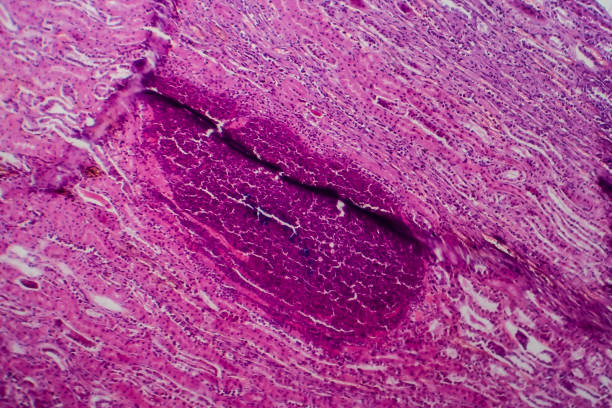

높은 요산수치는 먼저 신장에 부담을 줄 수 있습니다. 요산은 신장에서 처리되는데, 너무 많은 요산이 발생하면 신장의 부담이 크게 증가하게 됩니다. 이렇게 되면 신장 기능이 저하되고, 만성적인 신장질환의 위험성도 증가할 수 있습니다.